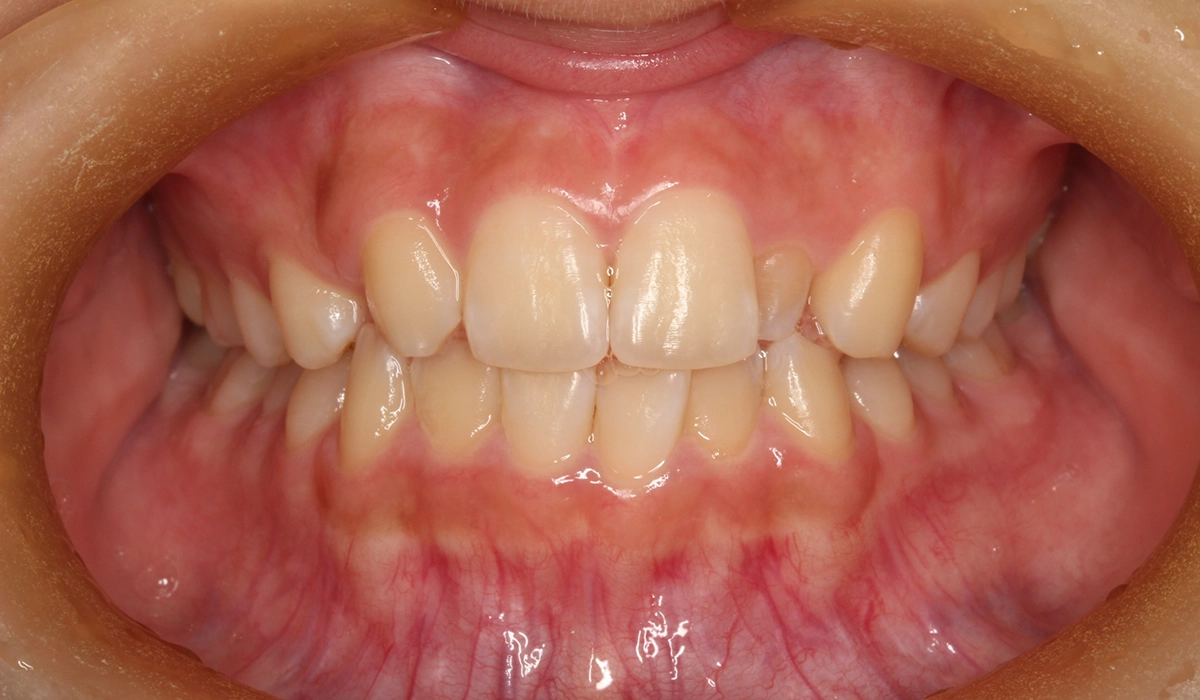

術前:正面

今回ご紹介する患者様は、上顎の歯並びのがたつきを気にされており、矯正検査後Ⅰ級叢生と診断いたしました。矮小歯があるため個性を生かして配列。

| 主訴 | 上顎の歯並びのがたつきが気になる |

| 治療内容 | 上顎の歯並びのがたつきを気にされており、矯正検査後Ⅰ級叢生と診断。矮小歯があるため個性を生かして配列。 |